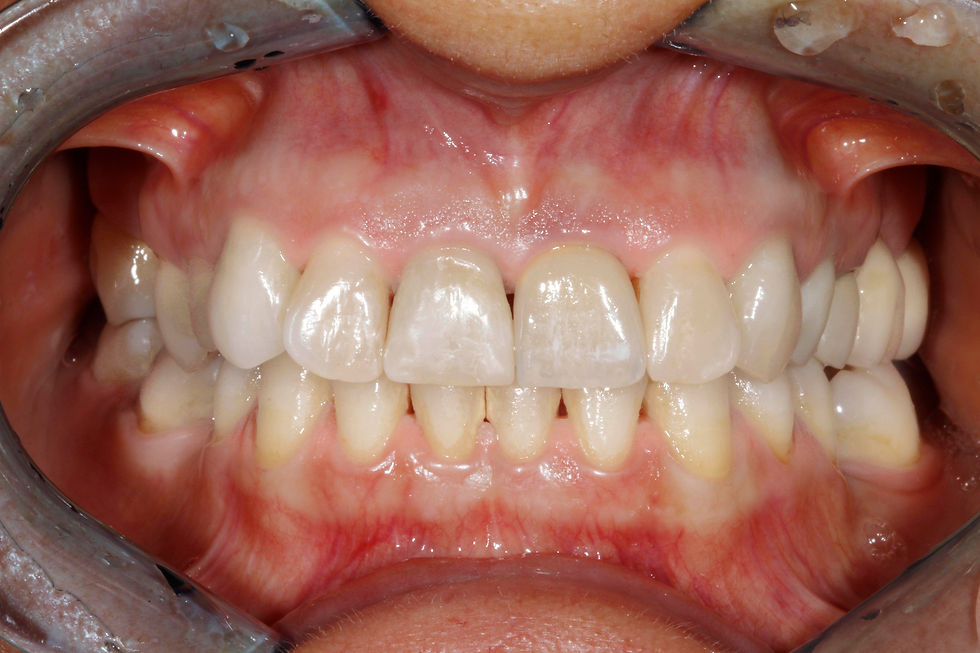

Clinical photo 4 months after surgery: parabolas are harmonized, and soft tissues are stable and healed.